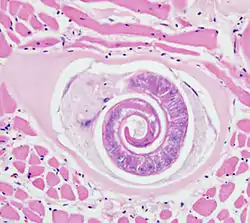

- Parásitos de animales

Distintas subespecies del género Trichinella producen una zoonosis llamada triquinelosis, por la cual un parásito coloniza el tejido muscular estriado de los mamíferos. El vehículo de infección es la ingesta de carne de animales infectados con quistes del nematodo. Dentro del quiste se aloja una larva arrollada formando una espiral. Al ingerir el quiste, las enzimas de la digestión liberan la larva. Esta se traslada en forma pasiva hacia el yeyuno por peristaltismo donde alcanza su estadio adulto. Allí se reproducen y la nueva camada de larvas perfora la mucosa intestinal y se protegen al formar un sincitio por fusión de un número aproximado de ciento veinte células. En el interior pasan por cuatro mudas hasta completar su desarrollo entre un día y un día y medio más tarde. Las larvas que eclosionan se transportan por la vía linfo-hemática por todo el huésped hasta alojarse en el músculo esquelético estriado.[50]

Los humanos son huéspedes ocasionales, frecuentemente por la transmisión vía ingesta de carne de cerdo infectada. La especie que produce mayores perjuicios a los humanos es Trichinella spiralis.[50]